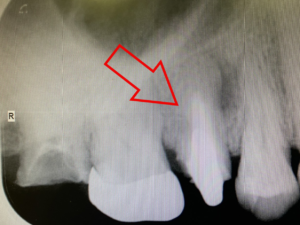

右の赤丸は、歯が抜けたまま放置されていた場所です。(左上7番)

こちらがインプラント治療を終えた歯です。